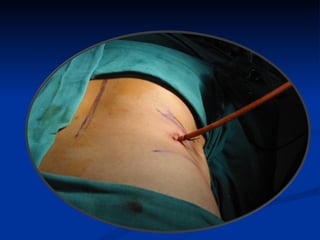

Steps for PCNL Retrograde ureteric catheterization  Fluoroscopy-guided percutaneous puncture(B-ultrasound for simple case) Tract dilation Lithotripsy Double-J stent and nephrostomy tube placement

Body position prone position (most cases) side-lying position ( obesity 、 cardiorespiratory  dysfunction ) supine position ( transplanted kidney )

Steps for PCNLRetrograde ureteric catheterization Fluoroscopy-guided percutaneous puncture(B-ultrasound for simple case) Tract dilation Lithotripsy Double-J stent and nephrostomy tube placement

Body position proneposition (most cases) side-lying position ( obesity 、 cardiorespiratory dysfunction ) supine position ( transplanted kidney )